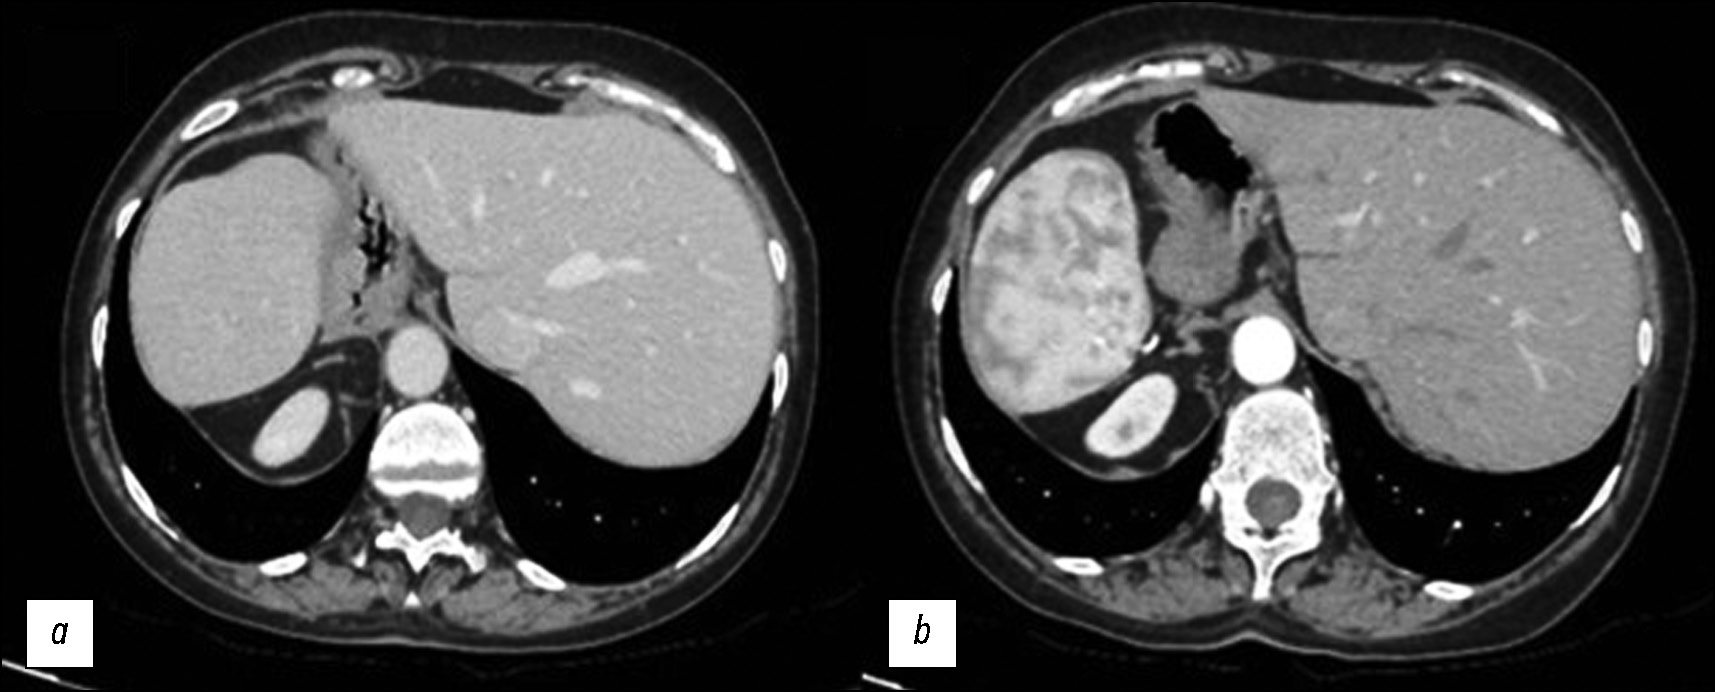

This case is not directly related to significant symptoms or acute problems due to SIT; instead, the interventions were focused on critical symptoms and the management and prevention of complications [12–16]. Biliary colic treatment aims to reduce pain with painkillers and antispasmodics to relieve symptoms (Fig. 5).

Fig. 5. The gallbladder appears with multiple calcific calculi. These CT images without (a) and with (b) contrast medium justify the left-sided abdominal pain.